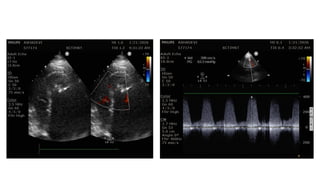

TTE

• LV-51/40

• IVS- 8/7

• EF-30%

• LA-31

• AO-29

• RWMA- AL/AW/Apex- Akinetic

• Apical VSR-4mm with L-R shunt (multiple fenestration

present), gradient-60mmHg

• Moderate RV dysfunction (TAPSE-11)

• MR 2+

• Moderate- severe LV Dysfunction